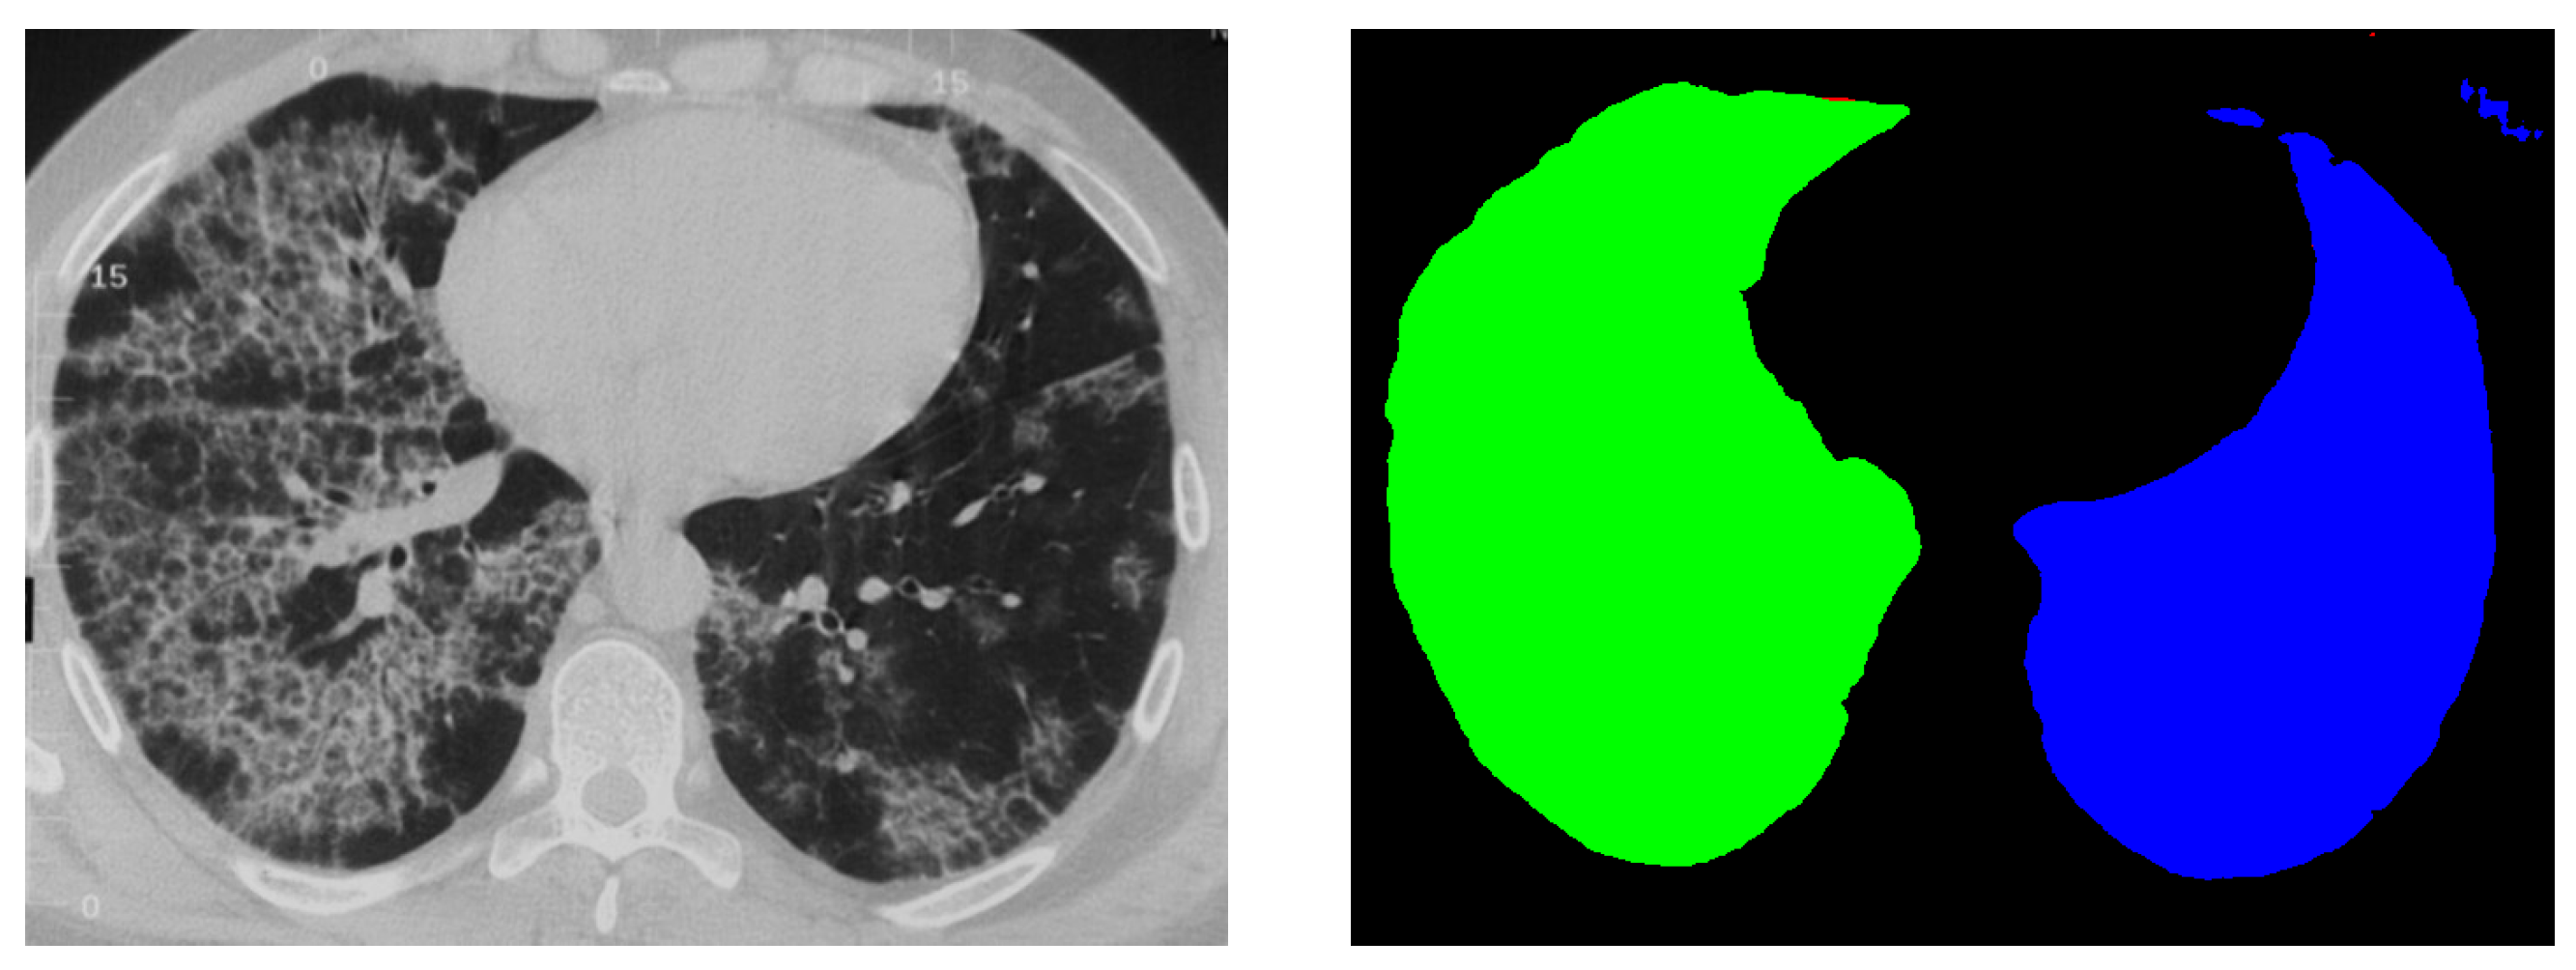

4.3. External Validation on PleThora Dataset